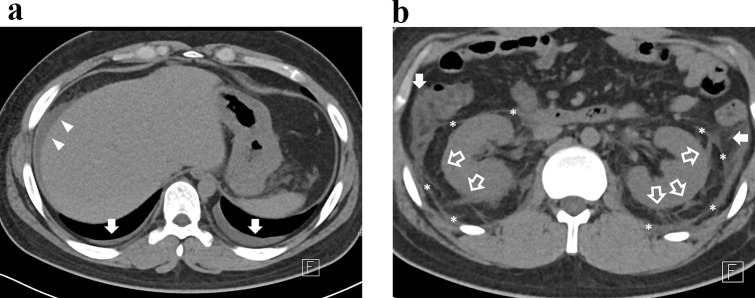

Methods: This retrospective study included 37 patients diagnosed with HFRS from January 2012 to December 2023 who had available clinical laboratory and abdominal CT data during the acute phase. The CT severity score (range 0-5) was based on perirenal fat stranding, pararenal fascia thickening, anterior pararenal space fat stranding, ascites, and pleural effusion. Correlations between the score and markers of inflammation, thrombocytopenia, proteinuria, and adverse outcomes-including nephrotic range proteinuria and renal replacement therapy (RRT)-were analyzed.

Results: The CT severity score exhibited moderate to strong correlations with markers of inflammation (white blood cell count, ρ = 0.65, p < 0.001), thrombocytopenia (platelet count, ρ = -0.54, p < 0.001), and proteinuria (urine protein-to-creatinine ratio, ρ = 0.56, p < 0.001). Higher scores were associated with increased nephrotic range proteinuria in Chi-squared test for trend (p-for-trend = 0.001). A one-point increase in the score significantly increased odds of requiring RRT in logistic regression analysis (odds ratio: 9.89, p = 0.047). The score achieved an area under the receiver operating characteristics curve of 0.819 for predicting RRT.